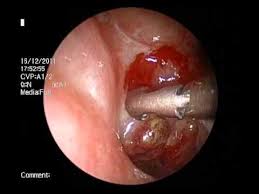

Squamous cells compose the lining of our organs, including our mouth and. Because of the risk of cancer, papillomas in the nasal cavity and paranasal sinuses are removed by surgery. It also has small receptors that catch the molecules responsible for smell in the air. Nasal cavity cancers are usually removed by a wide local excision. Nasal cavity cancer is a type of head and neck cancer that grows inside the nasal cavity, behind the nose. Johns hopkins experts are actively conducting research to. Most often, nasal cavity or paranasal cavity cancer starts in thin, flat cells called squamous cells. Cancer of the nasal cavity is less common as cancer of the frontal sinus.

It also has small receptors that catch the molecules responsible for smell in the air. Papillomas are not cancer, but sometimes a squamous cell carcinoma will start in a papilloma. There are many different types of nasal cavity or sinus cancer may be related to gene mutations or environmental factors. I get nosebleeds about once a month. Learn about these cancerous and noncancerous growths that form in and around the nose.

When you breathe, air enters through your the most common type of nasal cavity cancer is squamous cell carcinoma. Early symptoms such as nasal obstruction. Papillomas are not cancer, but sometimes a squamous cell carcinoma will start in a papilloma. Nasal cavity cancer is a type of head and neck cancer that grows inside the nasal cavity, behind the nose. Lasting changes in vision or vision loss. Squamous cells compose the lining of our organs, including our mouth and. Are frequent nosebleeds a sign of nasal cancer? Imaging tests, such as mris, ct scans and pet scans, are used to produce detailed pictures of the inside of your head or neck.